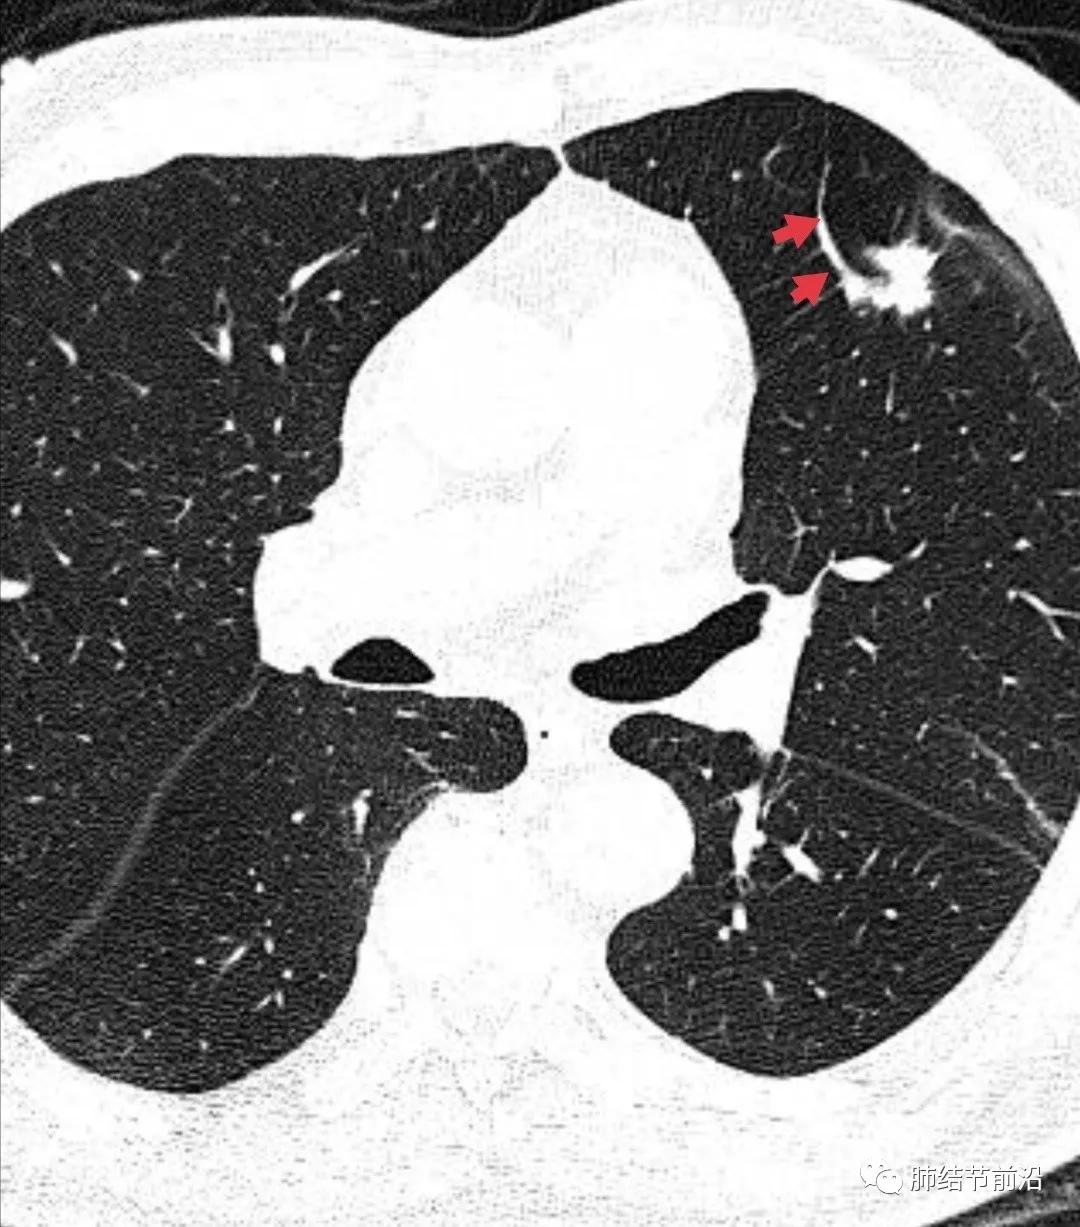

肿瘤组织需要氧供,新生血管是肿瘤的特征之一。传统的鉴别肺结节良恶性的标准之一就是血管集束征。然而在磨玻璃结节释放的血管生成因子并不强烈,新生血管不明显。则表现为诱导血管弯曲,出现明显有别于正常血管的弯曲现象,并向结节生长,称之为"血管弯"。这是肿瘤性磨玻璃/半实性结节很常见的特异性现象,出现这种表现,诊断磨玻璃/半实性结节为早期肺癌十拿九稳。“血管弯”名词引用自武汉市人民医院谭先华主任。

病例2:血管弯曲